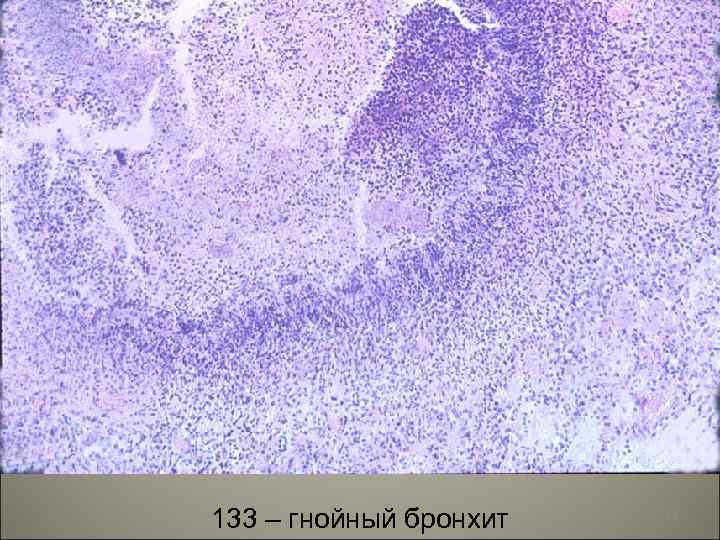

• I. Острые экссудативные бронхиты по характеру экссудата подразделяются: 1. серозно-катаральные, 2. гнойно-катаральные, 3. гнойные, 4. фибринозно-язвенные, 5. геморрагические. • II. Некротический бронхит. 20

133 – гнойный бронхит 24